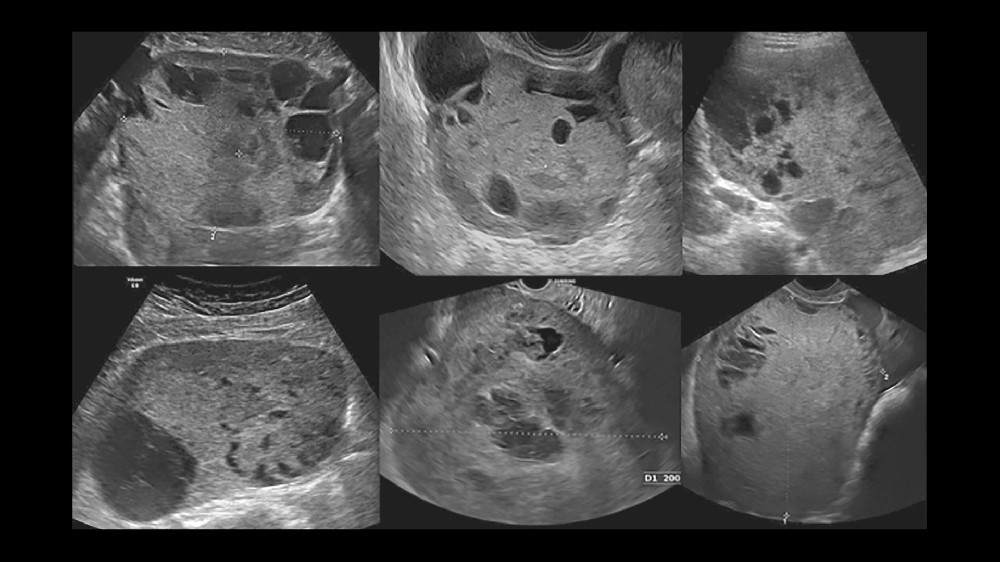

影像和活檢可提供確切證據,以進行精確的分期和治療規劃

女性卵巢增大或骨盆不適,通常會因為初期症狀不顯著而導致延遲診斷